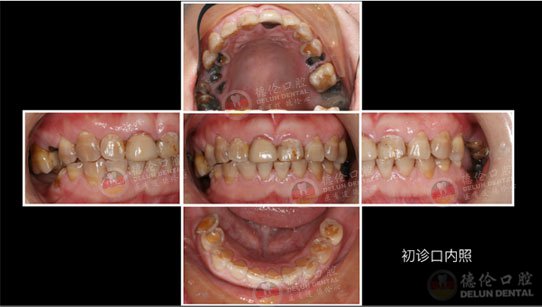

李医生诊疗案例